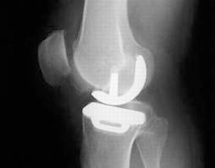

X-Ray showing Oxford Partial Knee Replacement

X-Ray of a medial Oxford Uni-compartmental Knee Replacement